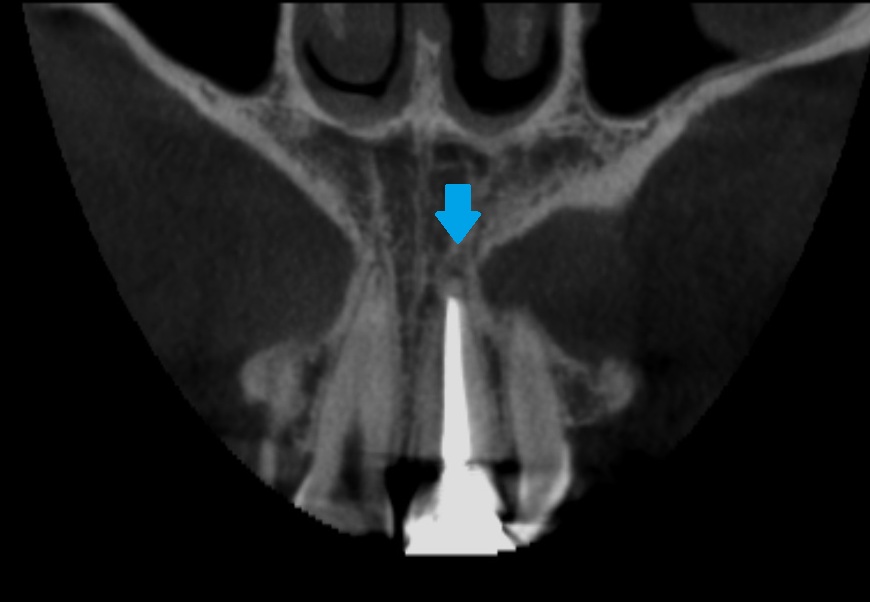

CT写真でさらに詳しく確認してみると、

正面と横側からの断面です。

神経を抜いてある歯を治療する際には、根の先で膿んでいないか(バイ菌が入っていないか)を確認する必要があります。

神経が無いので、虫歯が入り感染していても痛みを感じません。

もしバイ菌が入っている場合は、再度、根管治療を行ない、歯の中を消毒する必要があります。

今回は問題ないので、差し歯(かぶせ物と土台)だけやり直します。